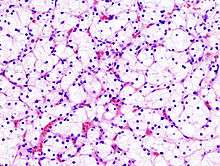

Histopathology

The gross and microscopic appearance of renal cell carcinomas is highly variable. The renal cell carcinoma may present reddened areas where blood vessels have bled, and cysts containing watery fluids.[54] The body of the tumour shows large blood vessels that have walls composed of cancerous cells. Gross examination often shows a yellowish, multilobulated tumor in the renal cortex, which frequently contains zones of necrosis, haemorrhage and scarring. In a microscopic context, there are four major histologic subtypes of renal cell cancer: clear cell (conventional RCC, 75%), papillary (15%), chromophobic (5%), and collecting duct (2%). Sarcomatoid changes (morphology and patterns of IHC that mimic sarcoma, spindle cells) can be observed within any RCC subtype and are associated with more aggressive clinical course and worse prognosis. Under light microscopy, these tumour cells can exhibit papillae, tubules or nests, and are quite large, atypical, and polygonal.

Recent studies have brought attention to the close association of the type of cancerous cells to the aggressiveness of the condition. Some studies suggest that these cancerous cells accumulate glycogen and lipids, their cytoplasm appear "clear", the nuclei remain in the middle of the cells, and the cellular membrane is evident.[55] Some cells may be smaller, with eosinophilic cytoplasm, resembling normal tubular cells. The stroma is reduced, but well vascularised. The tumour compresses the surrounding parenchyma, producing a pseudocapsule.[56]

The most common cell type exhibited by renal cell carcinoma is the clear cell, which is named by the dissolving of the cells' high lipid content in the cytoplasm. The clear cells are thought to be the least likely to spread and usually respond more favourably to treatment. However, most of the tumours contain a mixture of cells. The most aggressive stage of renal cancer is believed to be the one in which the tumour is mixed, containing both clear and granular cells.[57]